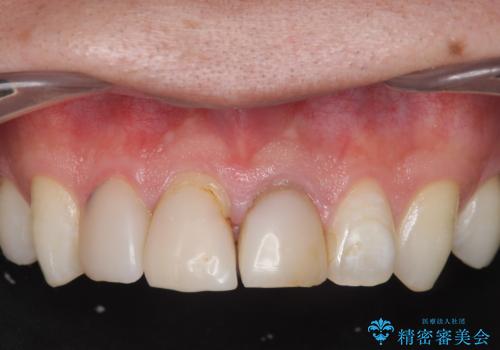

前歯の変色 審美性の改善